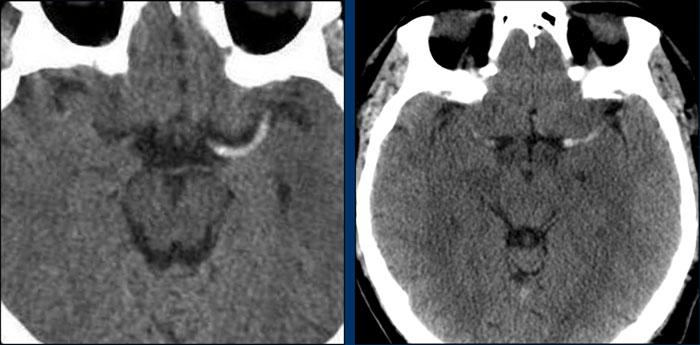

Huyết khối tăng tỷ trọng

Huyết khối tăng tỷ trọng là dấu hiệu điển hình trong bóc tách mạch máu, như được thấy ở hai bệnh nhân này.

Bất cứ khi nào bạn thấy những huyết khối tăng tỷ trọng đặc biệt cao như thế này, hãy nghĩ đến bóc tách mạch máu và cuộn xuống quan sát ngay phía dưới nền sọ.

Các huyết khối này gần như được cấu thành hoàn toàn bởi hồng cầu.